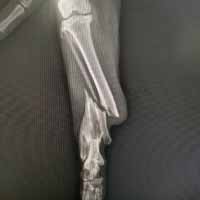

Yalıkavak veteriner kliniğimizde gerçekleştirdiğimiz ortopedik cerrahi uygulamalar:

Ortopedik cerrahi oldukça titizlik ve özen gerektiren cerrahi uygulamalardır. Diğer cerrahi disiplinlere nazaran asepsi ve antisepsi (sterilizasyon) konusunda ASLA hata kabul etmez. Eğer bu aşamada özensiz davranılırsa, postoperatif süreçte kemik dokunun iltihaplanmasına neden olup, kemiklerin kaynaması gecikmiş olur.